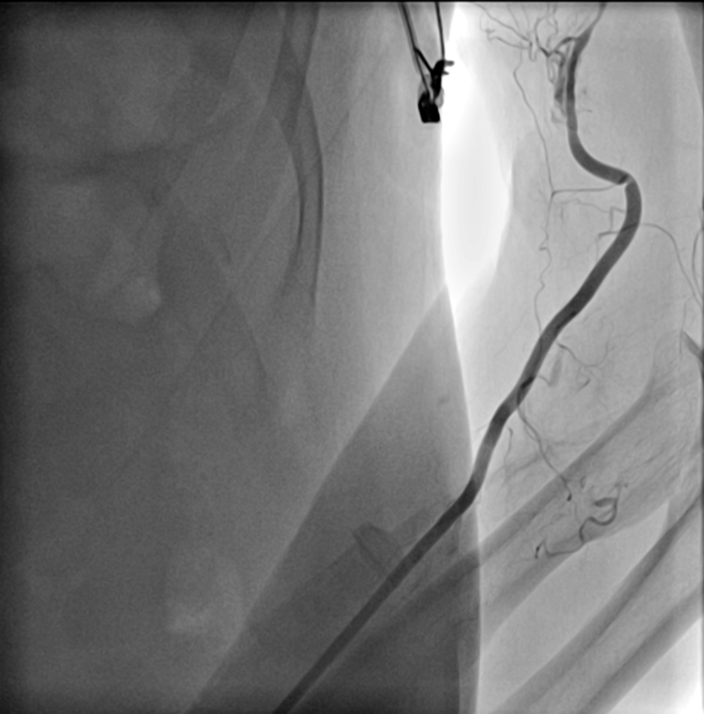

、慢性肾功能不全、双侧髂动脉曾植入支架。1月前外院冠脉造影提示三支血管均有重度钙化,左前降支(LAD)中段狭窄90%、对角支(D)狭窄80%、左旋支(LCX)近段狭窄90%、右冠状动脉(RCA)中段次全闭塞、远端慢性闭塞(视频1,图2-5)。

手术入路方面,双侧肱动脉均存在严重迂曲(视频9,图10),左锁骨下动脉重度狭窄,双侧髂动脉支架内增生明显,故此次选择右侧肱动脉路径。